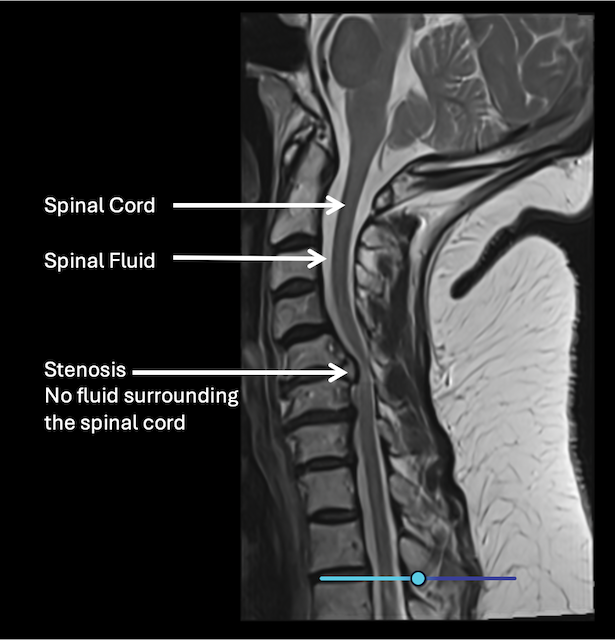

MRI shows the spinal cord, nerves, discs, and areas of narrowing. X-rays or CT scans may also be used to evaluate bone changes.

MRI scan showing a side view of the spine with labels pointing to the spinal cord, spinal fluid, and an area of stenosis with no fluid surrounding the spinal cord.